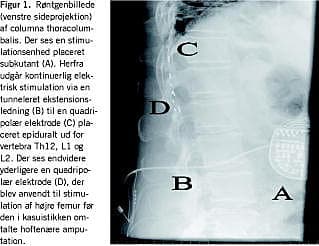

I 1999 havde patienten et faldtraume og pådrog sig et sår på amputationsstumpen. En infektion nødvendiggjorde en hoftenær amputation af femur med en efterfølgende forværring af fantom- og stumpsmerterne. På grund af ændret smertelokalisation blev en ny elektrode til SCS implanteret med godt resultat (Figur 1). Forbruget af opioider kunne nedtrappes til et minimum og gabapentin blev seponeret. Effekten af SCS var stabil frem til efteråret 2004, hvor stimulationsenhedens strømkapacitet var opbrugt, og patientens forbrug af ketomibedon hurtigt var blevet øget til 75 mg dagligt. Der blev efterfølgende foretaget en ukompliceret udskiftning af stimulationsenheden, og medicinforbruget normaliseres. Ved en ambulant kontrol 12 måneder senere var patienten fortsat tilfredsstillende smertelindret.

Patogenesen til CRPS er ufuldstændigt belyst, men synes at involvere en sympatikusdysfunktion [2-4]. SCS sker ved elektrisk stimulation af medulla. Stimulationen sker fra en pulsgenerator, der er implanteret subkutant, til en eller flere elektroder placeret epiduralt. Patienten kan med en fjernbetjening selv tænde og slukke for stimulationen og ændre intensiteten. Effekten af SCS til patienter med CRPS er veldokumenteret med acceptabelt respons hos 67% og en fordelagtig omkostningseffektivitetsprofil sammenlignet med konventionel terapi [3]. Mekanismen bag den smertebrydende effekt af SCS ved CPRS er ukendt, men sympatikusblokering synes at være en mulighed [4], en anden faktor kan være øget gamma-amino butyric acid (GABA)-medieret spinal hæmning af smerteimpulser [5].